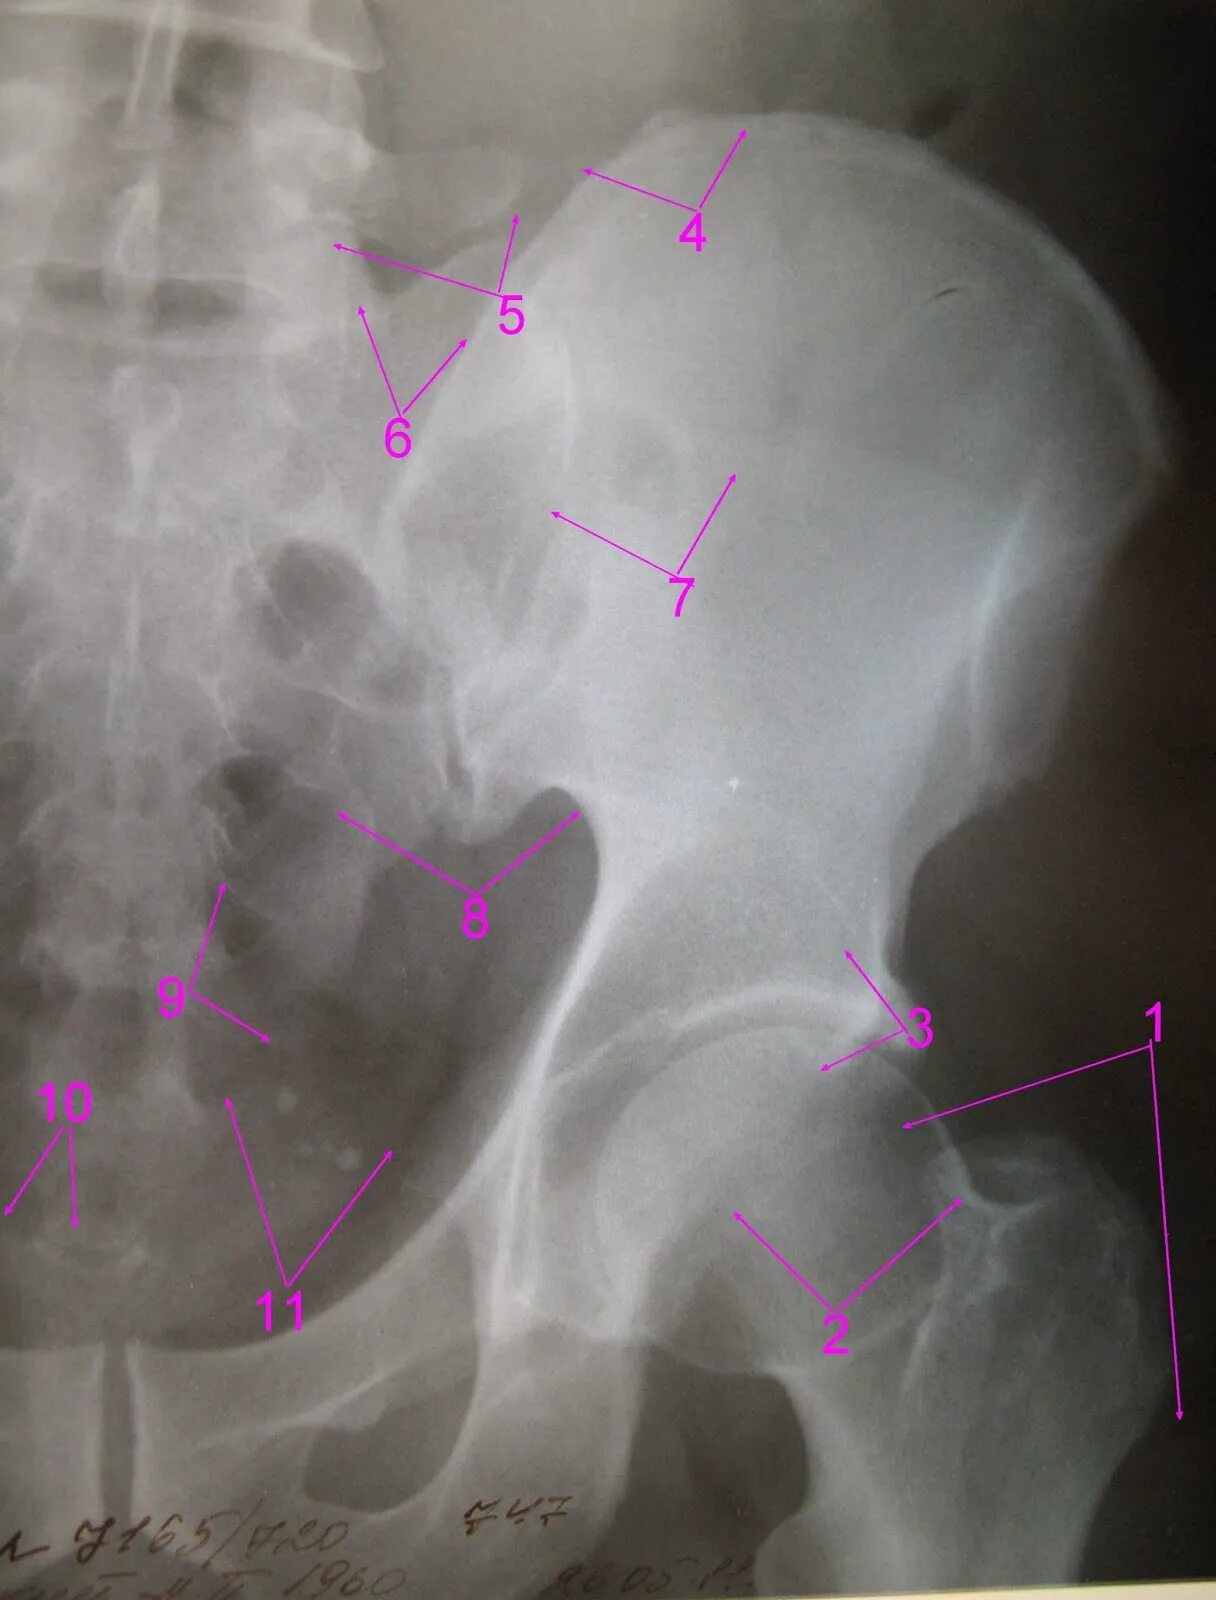

Перелом тазобедренной впадины